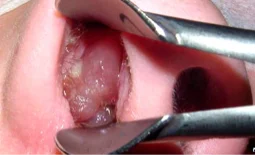

Le diagnostic de l’obstruction nasale est réalisé lors d’une consultation spécialisée ORL (oto-rhino-laryngologiste).

L’examen clé est l’endoscopie nasale ou la nasofibroscopie. C’est un examen de consultation simple, rapide, indolore. Il permet de visualiser avec précision l’intérieur des fosses nasales pour le diagnostic des anomalies architecturales et muqueuses.